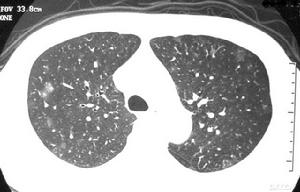

其他輔助檢查:影像學檢查:絕大部分患者在起病早期即有胸部X線檢查異常,多呈斑片狀或網狀改變。起病初期常呈單灶病變,短期內病灶迅速增多,常累及雙肺或單肺多葉。部分患者進展迅速,呈大片狀陰影。雙肺周邊區域累及較為常見,而胸腔積液、空洞形成以及肺門淋巴結增大等表現則較少見。對於胸片無病變而臨床又懷疑為本病的患者,1~2天內要複查胸部X線檢查。胸部CT檢查以玻璃樣改變最多見。肺部陰影吸收、消散較慢;陰影改變與臨床症狀體徵有時可不一致。